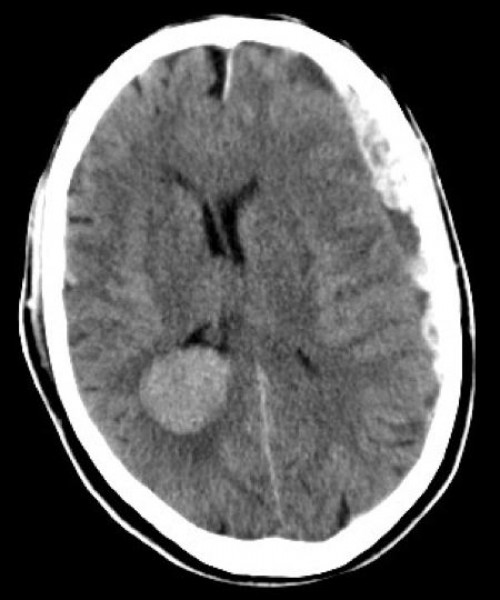

70-jähriger passionierter Radfahrer. Keinerlei ernsthafte Vorerkrankungen. Er ist mit dem Rad allein unterwegs auf seiner Tour durch Deutschland und kommt unbehelmt auf nasser Strasse zu Fall. Deutlich vigilanzgemindert wird er über den Schock-OP eingeliefert (Glasgow-Coma-Score 10).